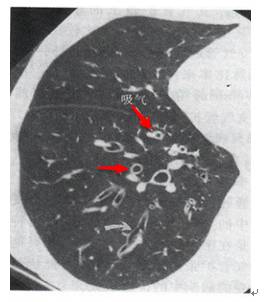

印戒征见于胸部CT扫描。它是由一小圆形软组织密度影邻接一围绕大圆形低密度空气影的环状软组织密度影构成。

在横断面CT扫描上,环状软组织密度影代表扩张的支气管壁,圆形低密度空气影代表扩张的支气管内气体。与环邻接的圆形软组织密度影代表与扩张支气管伴行的肺动脉的横断面影像。

2.CT表现 ①HRCT可见支气管壁增厚,管腔增宽,距胸膜下3cm的肺周边部也见到支气管;②可见“轨道征”和“印戒征”,扩张的支气管管径大于伴行的肺动脉直径,此时如支气管的走行方向与CT扫描平面垂直,即构成特征性的“印戒征”;如支气管走行与CT扫描平行时,表现为“轨道征”;③扩张的支气管内为黏液所充盈时,表现与血管伴行而粗于血管的柱状或结节状高密度影;④曲张型支气管扩张管壁不规则,可呈串珠状;囊状支气管扩张则表现为一组或多发性含气的囊肿,若囊内充满液体则呈现一串葡萄状,囊内出现气液平面是囊状支气管扩张最具特异性的征象